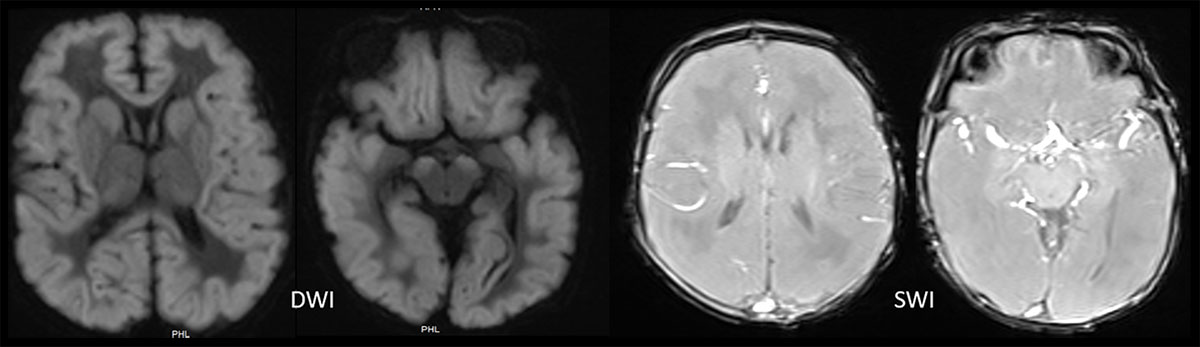

DWI: Diffuse, symmetric cortical thickening with widespread diffusion restriction, involving bilateral cortical and subcortical regions, basal ganglia, thalami, and cerebral peduncles.

SWI: Susceptibility-weighted imaging shows no hemorrhage